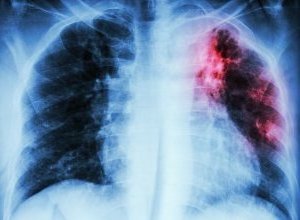

New ways to ensure TB patients comply with their treatment are desperately needed. The report says patients with the most straightforward form of the deadly infectious disease have to take a cocktail of drugs over a six-month period – and if they fail to stick to the regime, they risk the disease returning in a drug-resistant form.